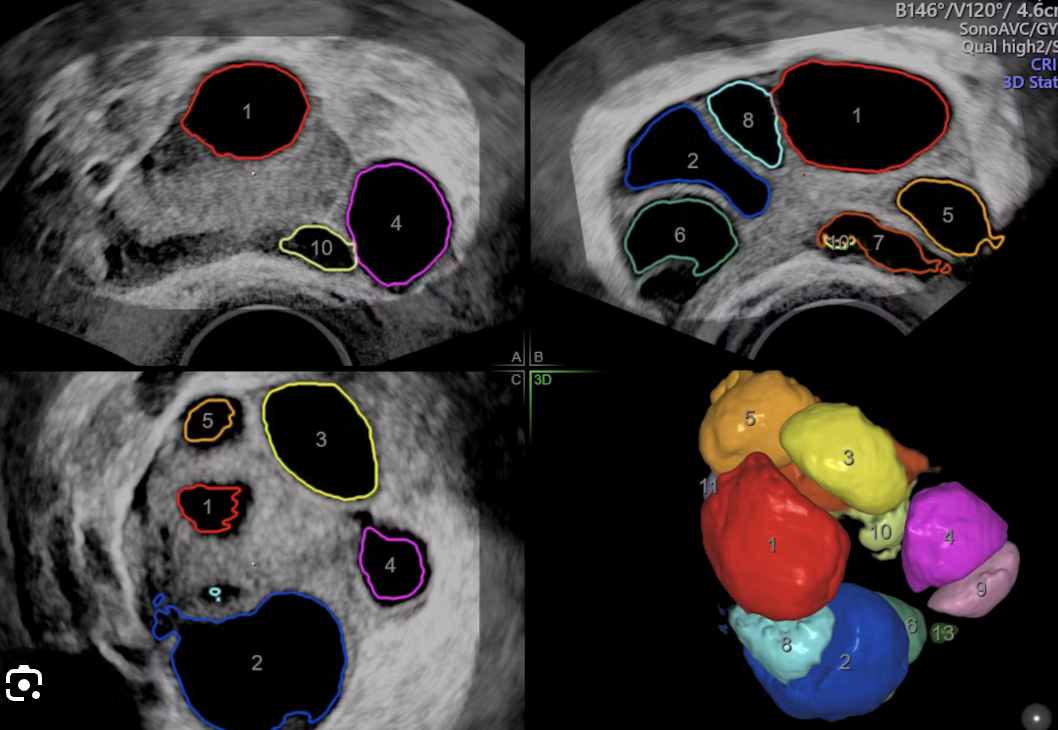

Fertility ultrasound scans include follicle tracking, antral follicle count, endometrial thickness, uterus, and ovaries.  A baseline fertility scan, which includes an antral follicle count (AFC), is a transvaginal ultrasound performed early in the menstrual cycle (days 2–5) to assess ovarian reserve and pelvic anatomy before fertility treatment begins. This scan helps fertility specialists plan treatment by counting the number of small, fluid-filled sacs (antral follicles) containing immature eggs in the ovaries. The count, combined with other tests like an AMH blood test, provides information about a woman's potential egg supply and how she might respond to fertility medications.

Antral Follicle Count (AFC): This is the primary purpose of the scan, involving counting the number of antral follicles in each ovary.

A follicle is a fluid filled sac which contains the egg. A follicle tracking scan is performed from Day 6 to 9 of your menstrual cycle to aid fertility treatment. Ultrasound technology can determine how many follicles there are and when egg extraction is best performed.

The shape, size and number of the antral follicles will be assessed and measured.

Follicle tracking scans are performed to monitor ovulation. In any one cycle there can be multiple ultrasound scans. The scan measures developing follicles within the ovaries throughout a cycle, usually with ovulation induction. It is important to avoid hyper-stimulation of the ovaries. The measurements include endometrial thickness (lining of the uterus) as this will influence whether the embryo is able to implant. This scan is often undertaken prior to fertility treatment, it provides guidance about the timing of treatment. The scan will measure the endometrium (womb lining) to access the suitability of proceeding with fertility treatment.